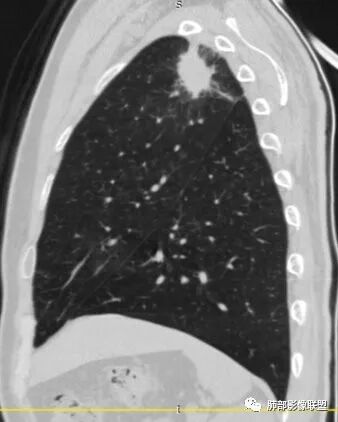

1、患者老年男性,无明显临床症状。

2、病灶位于左肺上叶尖后段,符合肺结核好发部位。

3、病灶密度不均,可见钙化点,未显示空洞或液化。边缘收缩,U型凹陷、桃尖征、细长毛刺以及较长棘状突起。宽基底与胸膜相连,邻近胸膜广泛性增厚(未见栽赃侵入)。可见卫星病灶,周围的磨玻璃影比较松散,炎性病变征象多,符合结核的CT表现。

4、部分区域膨隆,未见支气管截断,肺门纵隔未见肿大淋巴结等,恶性征象少。

5、结合其无临床症状、病灶形态、病灶位置及发病率,结核居多,最后诊断在大家意料之中。